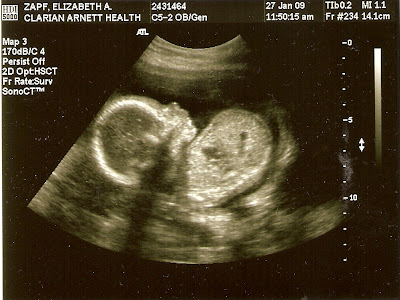

So, here is “New Baby” at 20 weeks:

I didn’t add any captions because the ultrasound tech did such a lovely job of it, I didn’t want to attempt to out-do her.